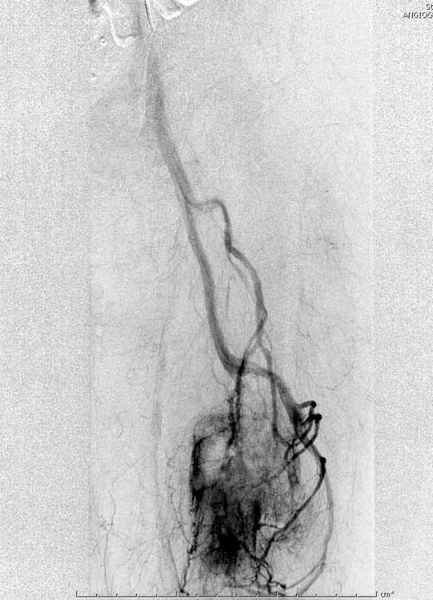

Для предупреждения кровотечения во время рассверливания, за день до операции провели эмболизацию сосудов питающий метастаз. http://radiology.rsnajnls.org/cgi/reprint/150/3/673.pdf (7-11, 12-15-16)

С минимальным рассверливанием и ретроградным методом провели остеосинтез бедра 12 мм гвоздем. (17-20)

Кровопотеря во время операции меньше 100 мл.